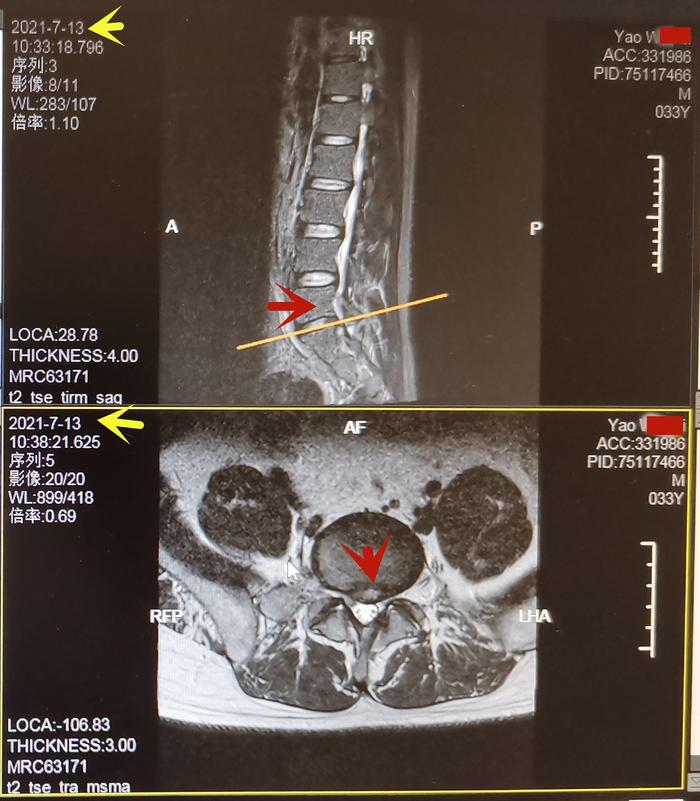

姚先生l5-s1椎间盘突出,红箭头.图5.姚先生训练.3.